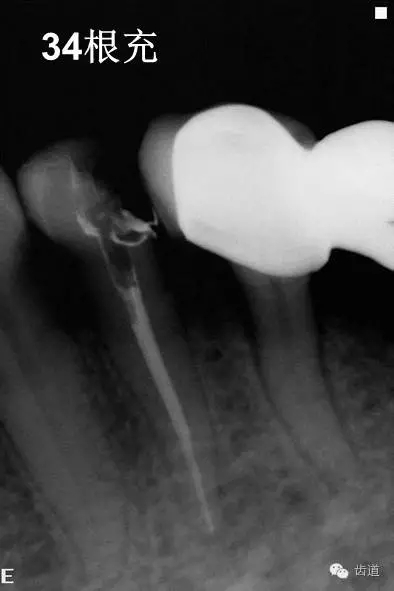

3、34術(shù)前片顯示遠(yuǎn)中面暗影近髓

4、34常規(guī)根管治療。(2013年8月)